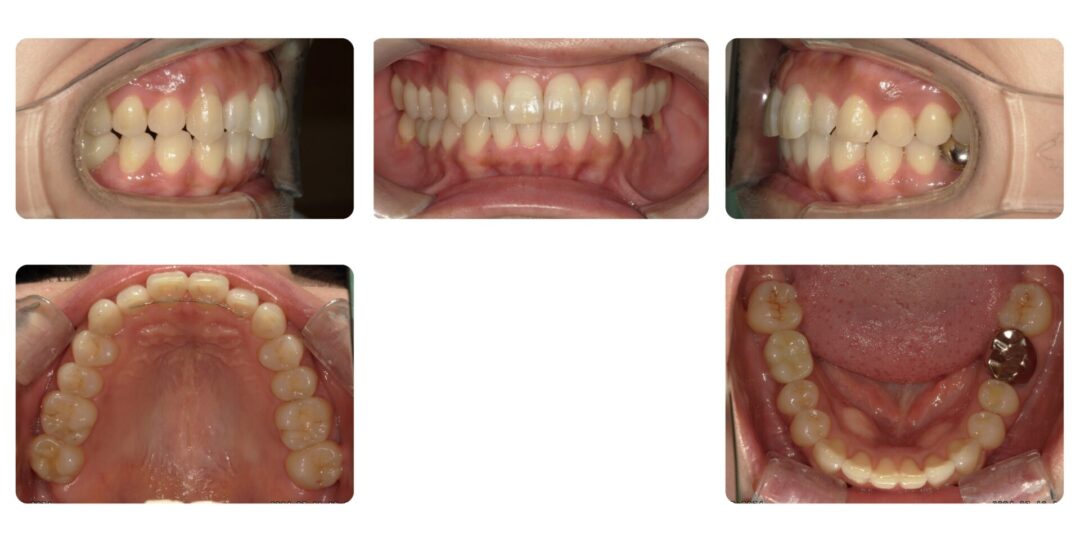

矯正治療後

成人歯科矯正 非抜歯 インビザライン矯正

3年1ヶ月

自由診療 基本料金インビザライン矯正¥880,000(開始当時)

インビザライン矯正のための精密検査¥22,000、処置料¥5,500